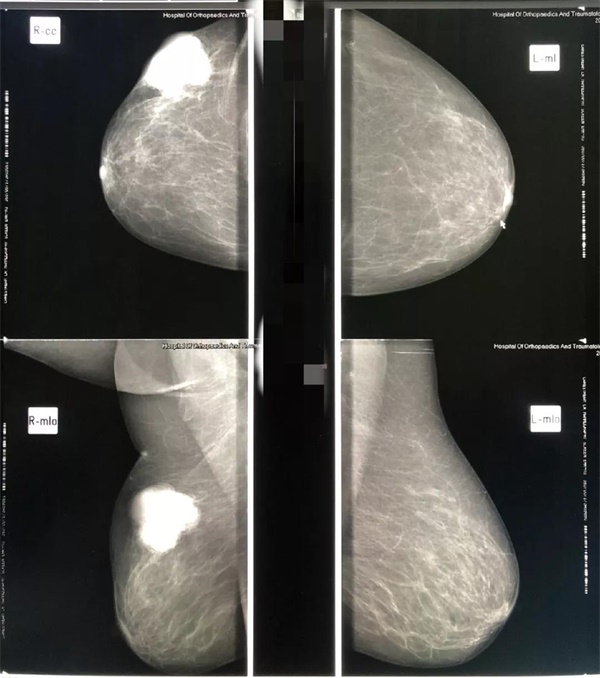

隨著生活水平的提高,乳腺癌的發(fā)病率越來越高,而且有年輕化的趨勢,已成為女性健康的一大殺手,所以,乳腺疾病的早發(fā)現(xiàn)、早診斷、早治療對保護女性健康具有十分重要的意義。

遼陽二院放射科乳腺鉬靶檢查設備先進,由放射科科主任劉曉威主檢,

診斷精準,服務熱情。

關(guān)愛女性健康從關(guān)愛乳腺做起

鉬靶檢查為女性健康保駕護航